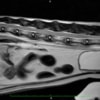

■ MRI検査

第5-6腰椎間で右側神経根が腫大し、脊柱管内に連続した腫瘤病変が認められました。脊髄および馬尾神経は右側から重度に圧迫されていました。

MRI検査所見

MRI 2